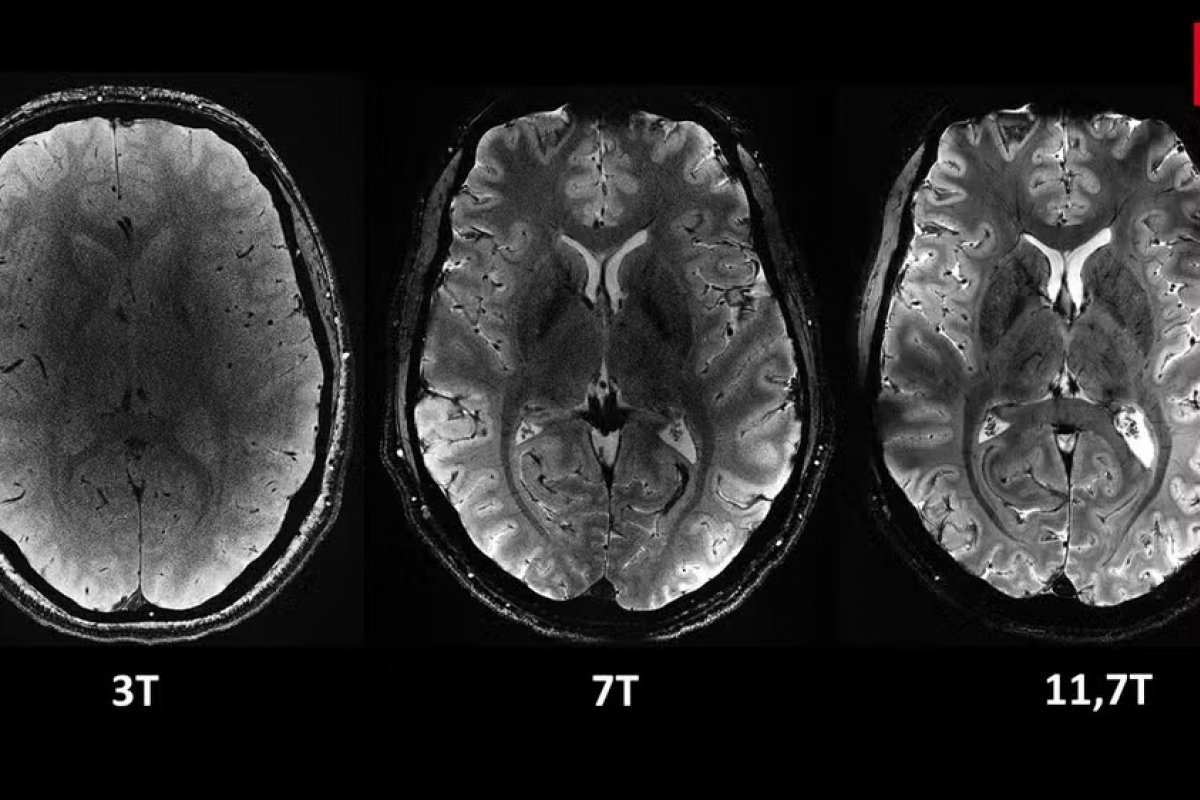

O campo magnético do scanner atinge incríveis 11,7 teslas, permitindo uma precisão até 10 vezes maior do que os aparelhos convencionais, comumente utilizados em hospitais.

Com essa potência, os pesquisadores podem visualizar detalhes minuciosos do cérebro, como vasos sanguíneos no córtex cerebral e estruturas do cerebelo que antes eram quase invisíveis.